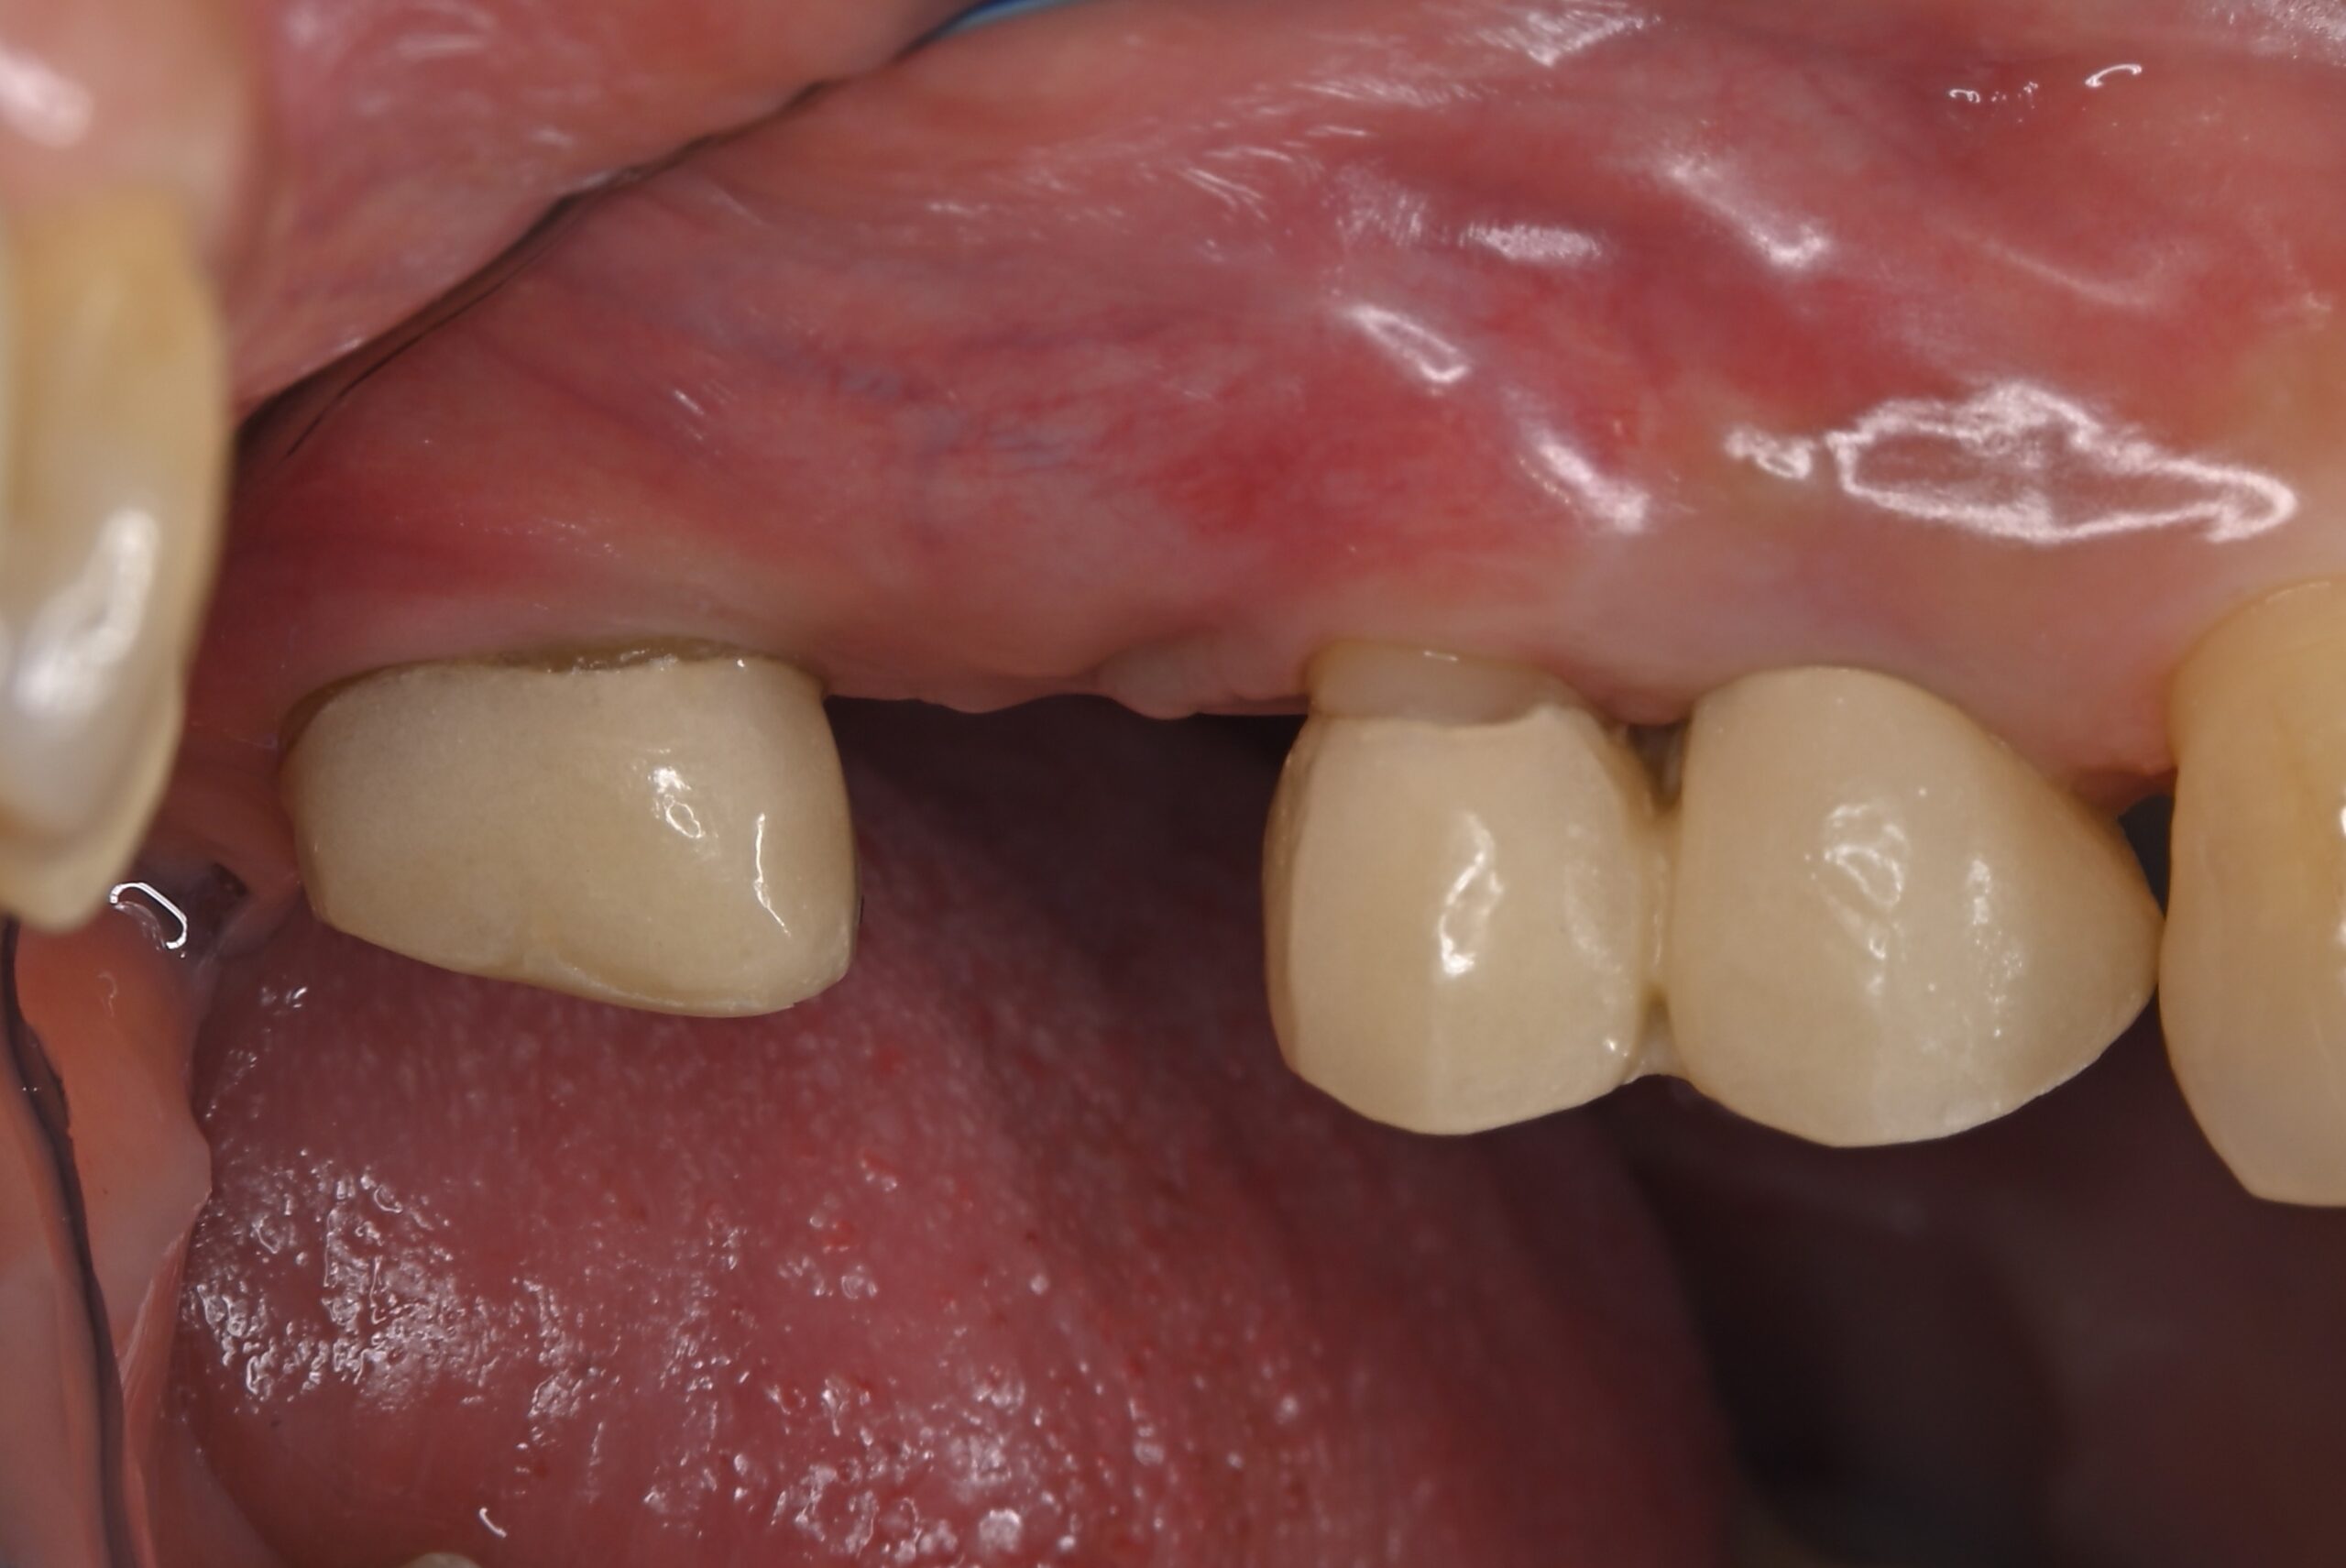

症例1:パーフォレーションリペア症例

(歯の中に大きな穴が空いてしまっているのを埋めて再生を促す治療)

AFTER |

人為的根穿孔を起こした部分に感染を起こしており、歯周ポケットが9㎜ありました。 ラバーダム防湿とマイクロスコープを使用して丁寧に治療を行いました。 殺菌性があり歯を補強することのできるMTAという根管充填材料を使用して、歯周ポケットは2㎜に改善しました。 |